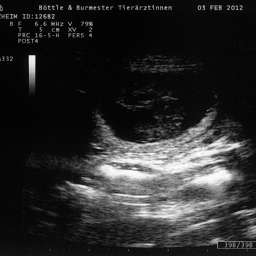

3.2.2012, 32.Tag: Der Ultraschalltermin ist vollbracht: Juhu, wir werden Eltern!!!

Aus Herzklopfen wurde Herzrasen und dann endlich, kurz vor der Herztablette, zeigte uns der Ultraschall 5 KLEINE WUNDER, gesunde Fruchthüllen, mit lebendigem Innenleben und pochendem Herzen. (...passte sehr gut zu unseren...)Wieviele es letztendlich werden, bleibt eine riesige Überraschung.

Bitteschön, ein kleines Filmchen mit dem Titel: "5 auf einen Streich, oder wie es in den Bauch hineinschallt, schallt es auch wieder hinaus."

4.2.2012, 33.Tag: Hier sind also die Fotos der kleinen Flauschmonster in ihren Höhlen.

Sucht Euch doch schon mal einen aus: